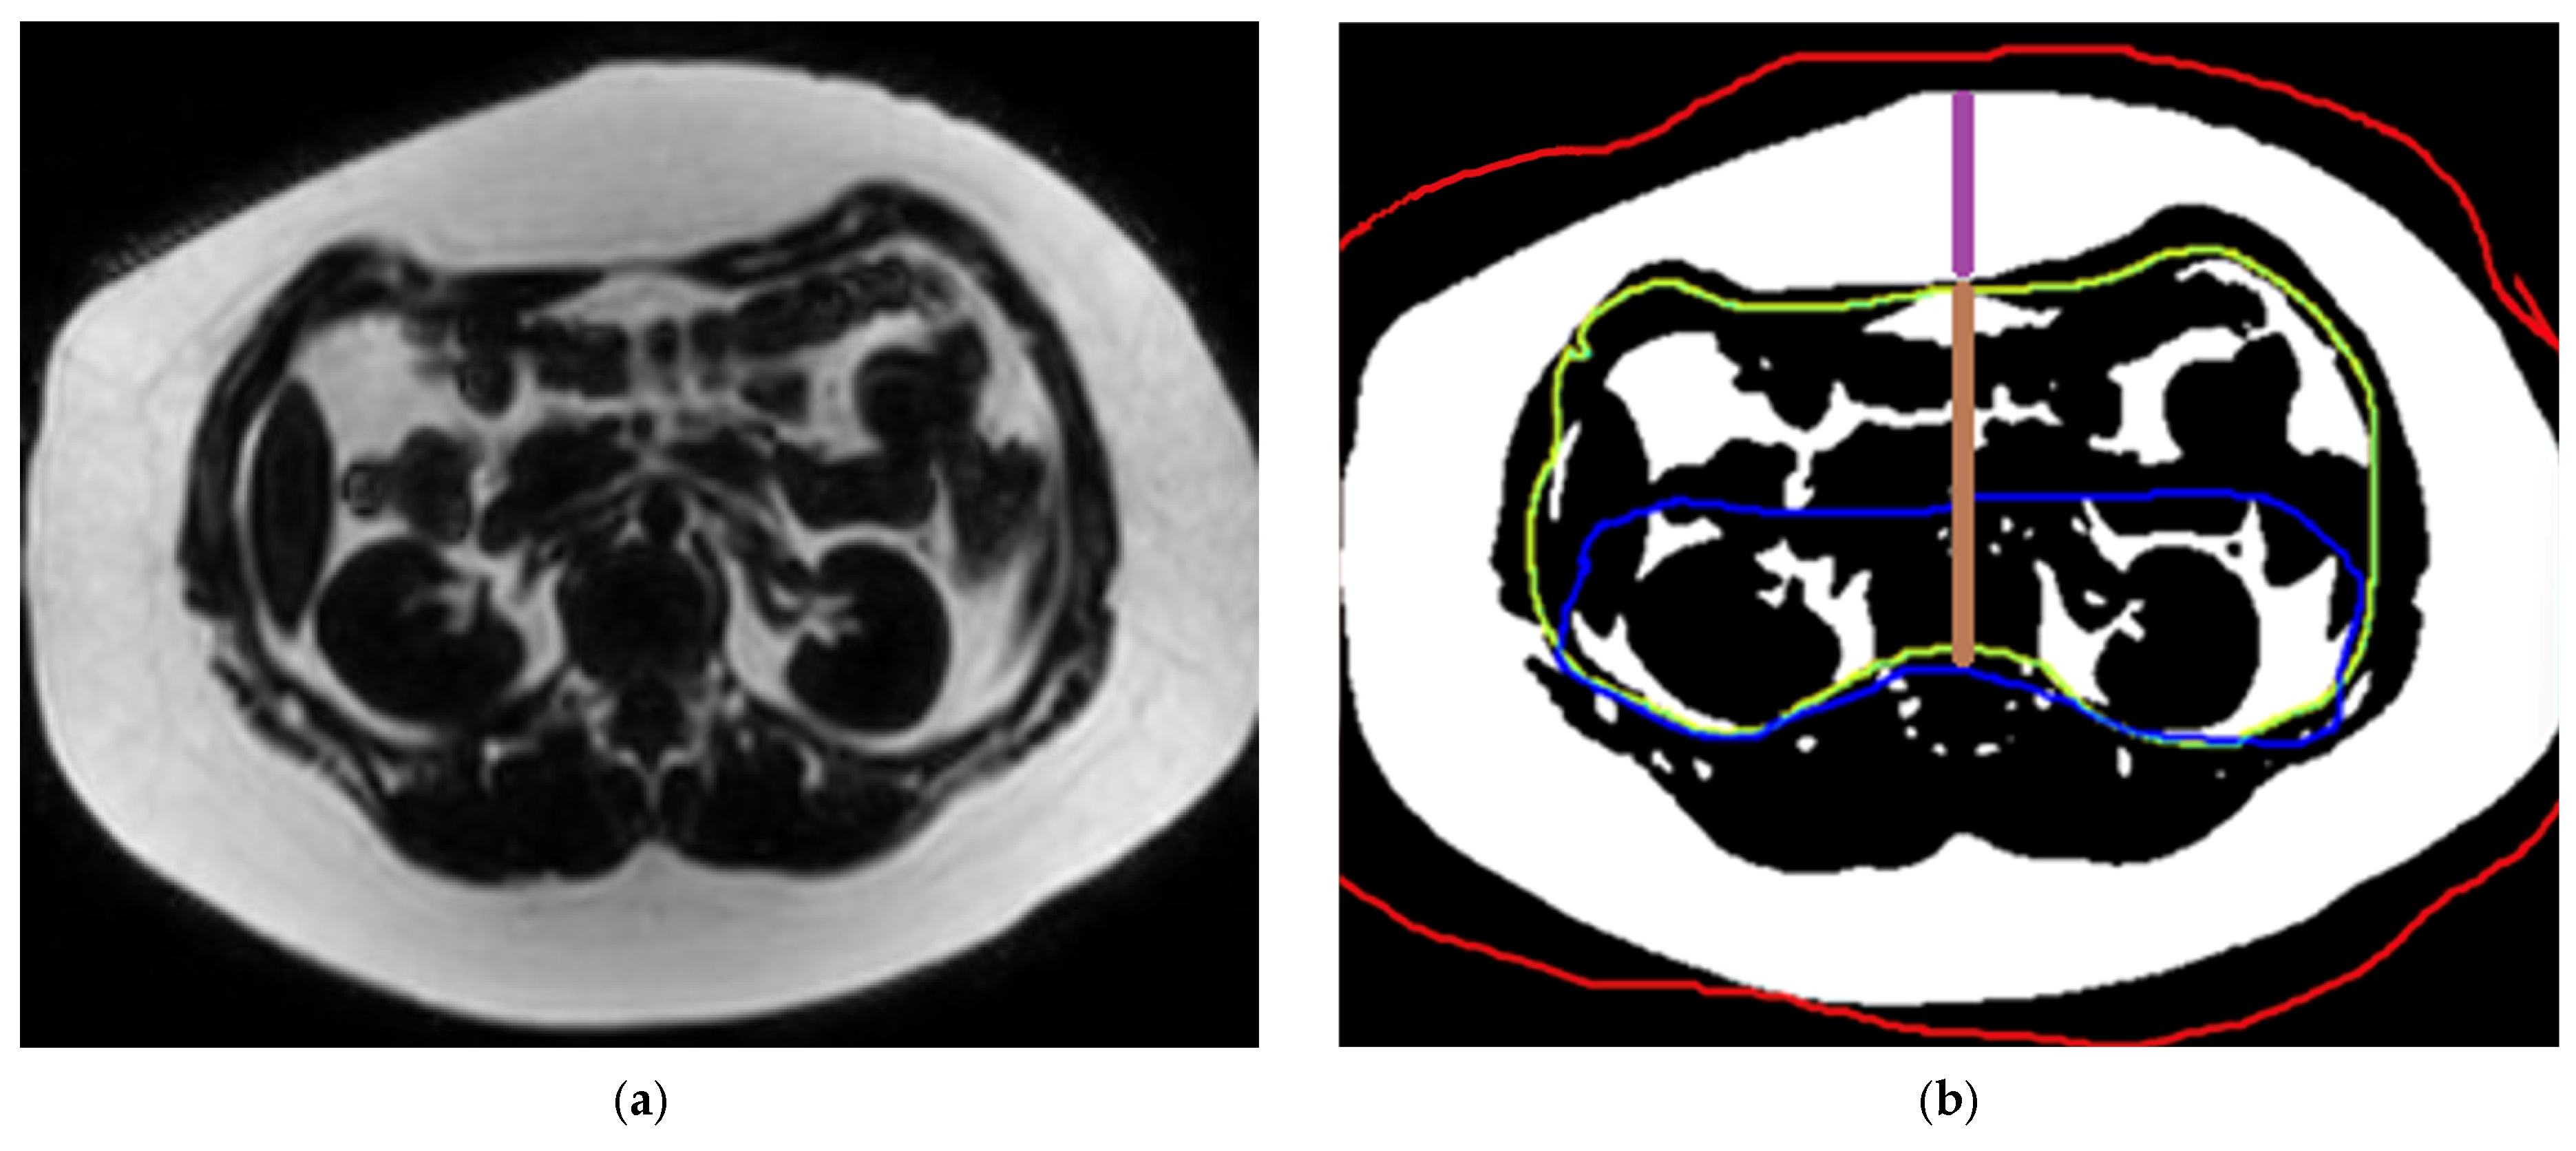

- Liver and pancreas volumes

2.3.3. Measurement of Abdominal Fat Compartment Surface Area and Thickness

2.3.4. Liver Elastography